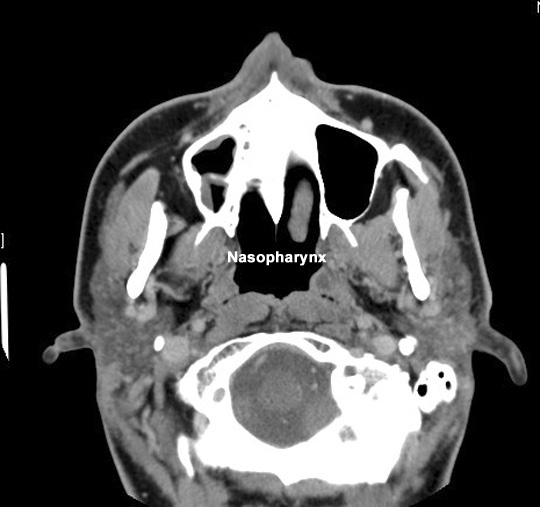

Identify the nasopharynx. Click the image for labeling.